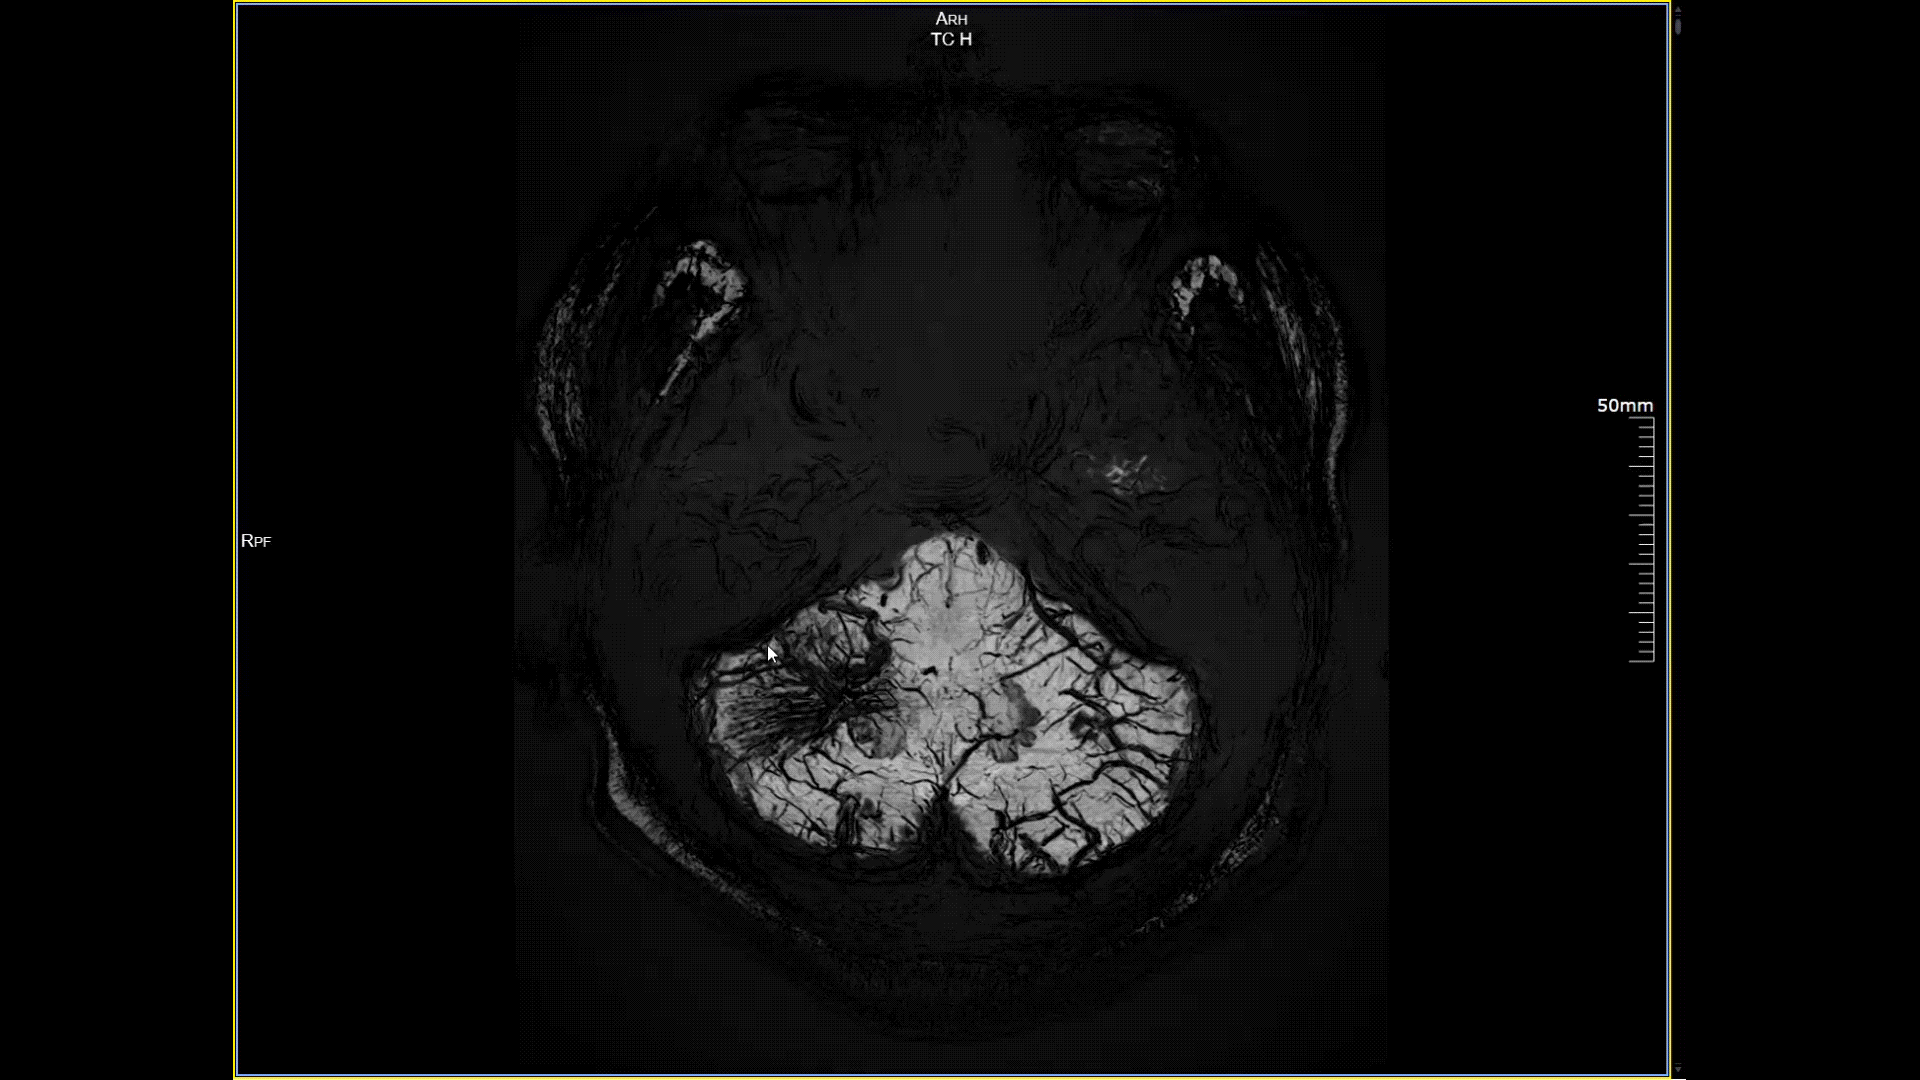

4D非造影剂头颅血管成像

磁敏感成像SWI,分辨率0.2*0.2mm

5.0T磁场强度远高于其他设备,使得氢原子核在磁场中的响应信号极大地增强。这就像在安静的房间里能听清细微的声音一样,高信噪比能让医生看到更微小、更模糊的病变结构。例如上述患者的检查,该设备可以呈现0.2x0.2毫米高分辨率的图像以及动态显示血管走行,使得病变血管的细微解剖结构、分布及其与周边脑组织的关系得以直观呈现,为临床医生进行精准诊断并制定后续治疗方案提供了重要的影像学依据。